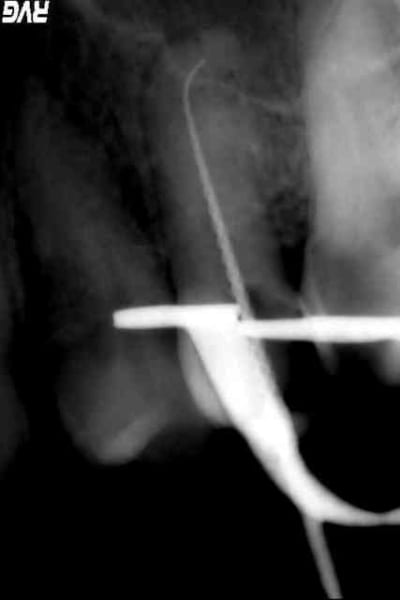

il y a 2 ans, avec abscence d'image radio et impossiblite de passer dans le canal, vous ne l'auriez pas faite la couronne?

> l'embetant c'est que j'ai essayé de reprendre le

> ttmt endo il y a 2 ans sans succes...

moi je l'adresserais à un endo exclusif qui posséde un micro.